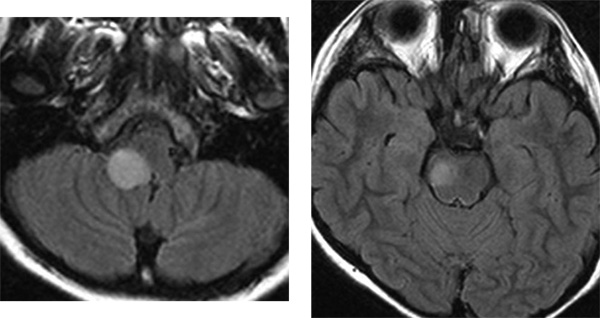

11歳の時のMRI

延髄の病変(左側)だけが増大していますが,あわてて治療しません